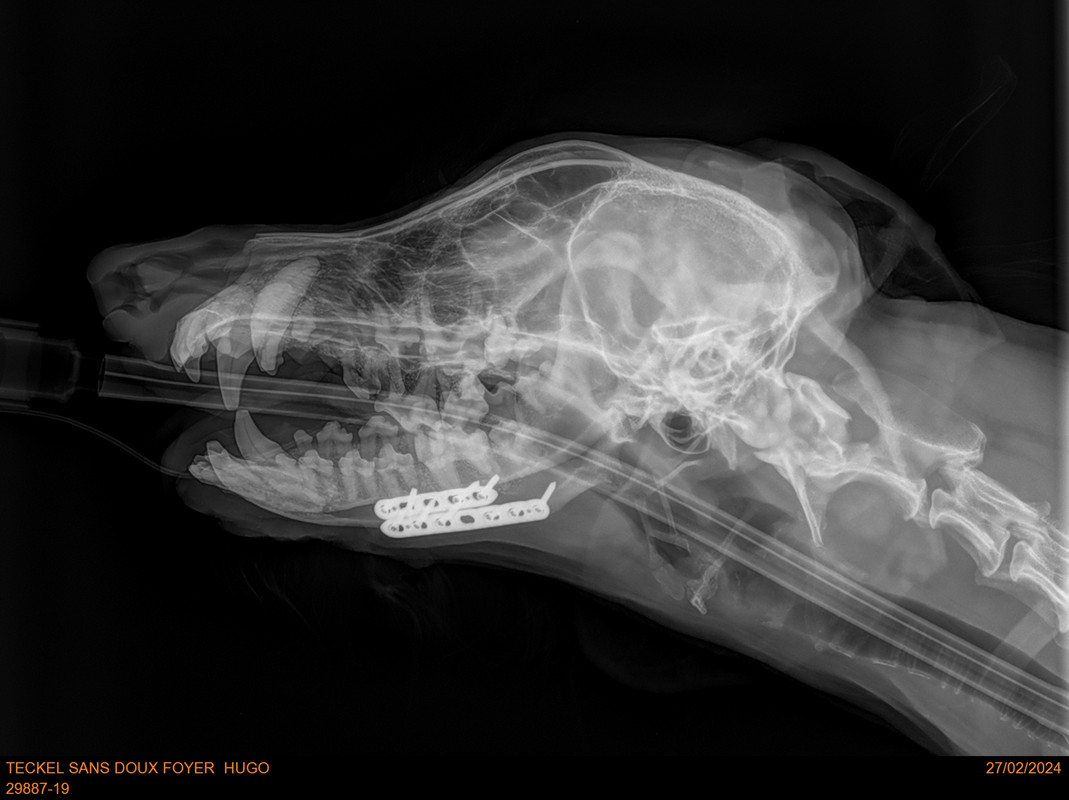

Voici la radio avant que les plaques soient otees ainsi que le compte rendu.

[Image: Hugo-radio.jpg]